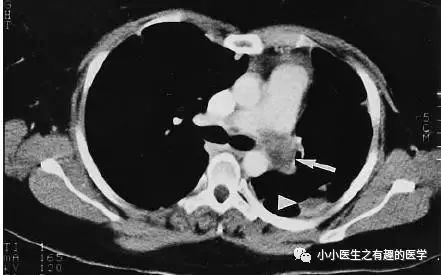

首先,来看看这个患者。美国康涅狄格州立大学报道,58岁男性,咳嗽,劳力性呼吸困难,进行性双侧下肢水肿2月。

A 58-year-old man presented with 2 months of cough, dyspnea on exertion, and progressive bilateral lower extremity edema.

这是什么?妥妥的肺栓塞啊,还能有啥?

怎么办?肿么办?别慌,米国人民的治疗和我们一样。抗凝治疗,2周后,患者呼吸困难加重返院。

He was treated expectantly with anticoagulants for pulmonary embolism but returned 2 weeks later with worsening dyspnea and echocardiographic evidence of right heart failure.

行动脉血栓内膜剥脱术,然而结果示黏液性梭形细胞肉瘤。

Surgical thromboendarterectomy revealed a high-grade myxoid spindle cell sarcoma.

是的,这不是肺栓塞,这是肺动脉内膜肉瘤。这不是扯蛋肺栓塞,这是扯蛋肺动脉肿瘤。扯蛋是肯定的,然而,血栓且不肯定。